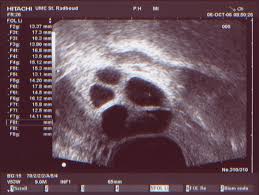

Buik is weer stil gevallen, ik voel geen geduw meer hopelijk is alles in orde...nog 4 keer slapen en dan mag ik eikes tellen....hopelijk!!!! Bekijk de afbeelding op ware grootte.

Dus we hopen dat het er ongeveer zo zal uitzien...mag ook ietske meer zijn